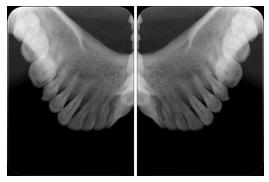

2. A patient requests cosmetic surgery to enhance their facial appearance. The case requires consultation between an orthodontist in New York and an oral surgeon in California. The cephalometric series of 2D projections constructed from the volumetric CT data that is used for the discussion is arranged by a Structured Display for transfer between the two practitioners.

Cephalometric Series Structured Display

Figure OO-2. Cephalometric Series Structured Display